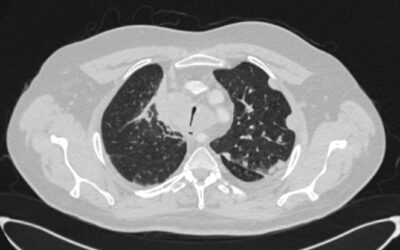

Клапанная бронхоблокация; Кровотечение из туберкулезных каверн легкого

Клапанная бронхоблокация; Кровотечение из туберкулезных каверн легкого Больной 57 летний мужчина. В 2013 году был лечен по поводу туберкулеза легких. Несколько месяцев назад у него появилось кровохарканье с эпизодами кровотечения. Пациент постоянно находится на...